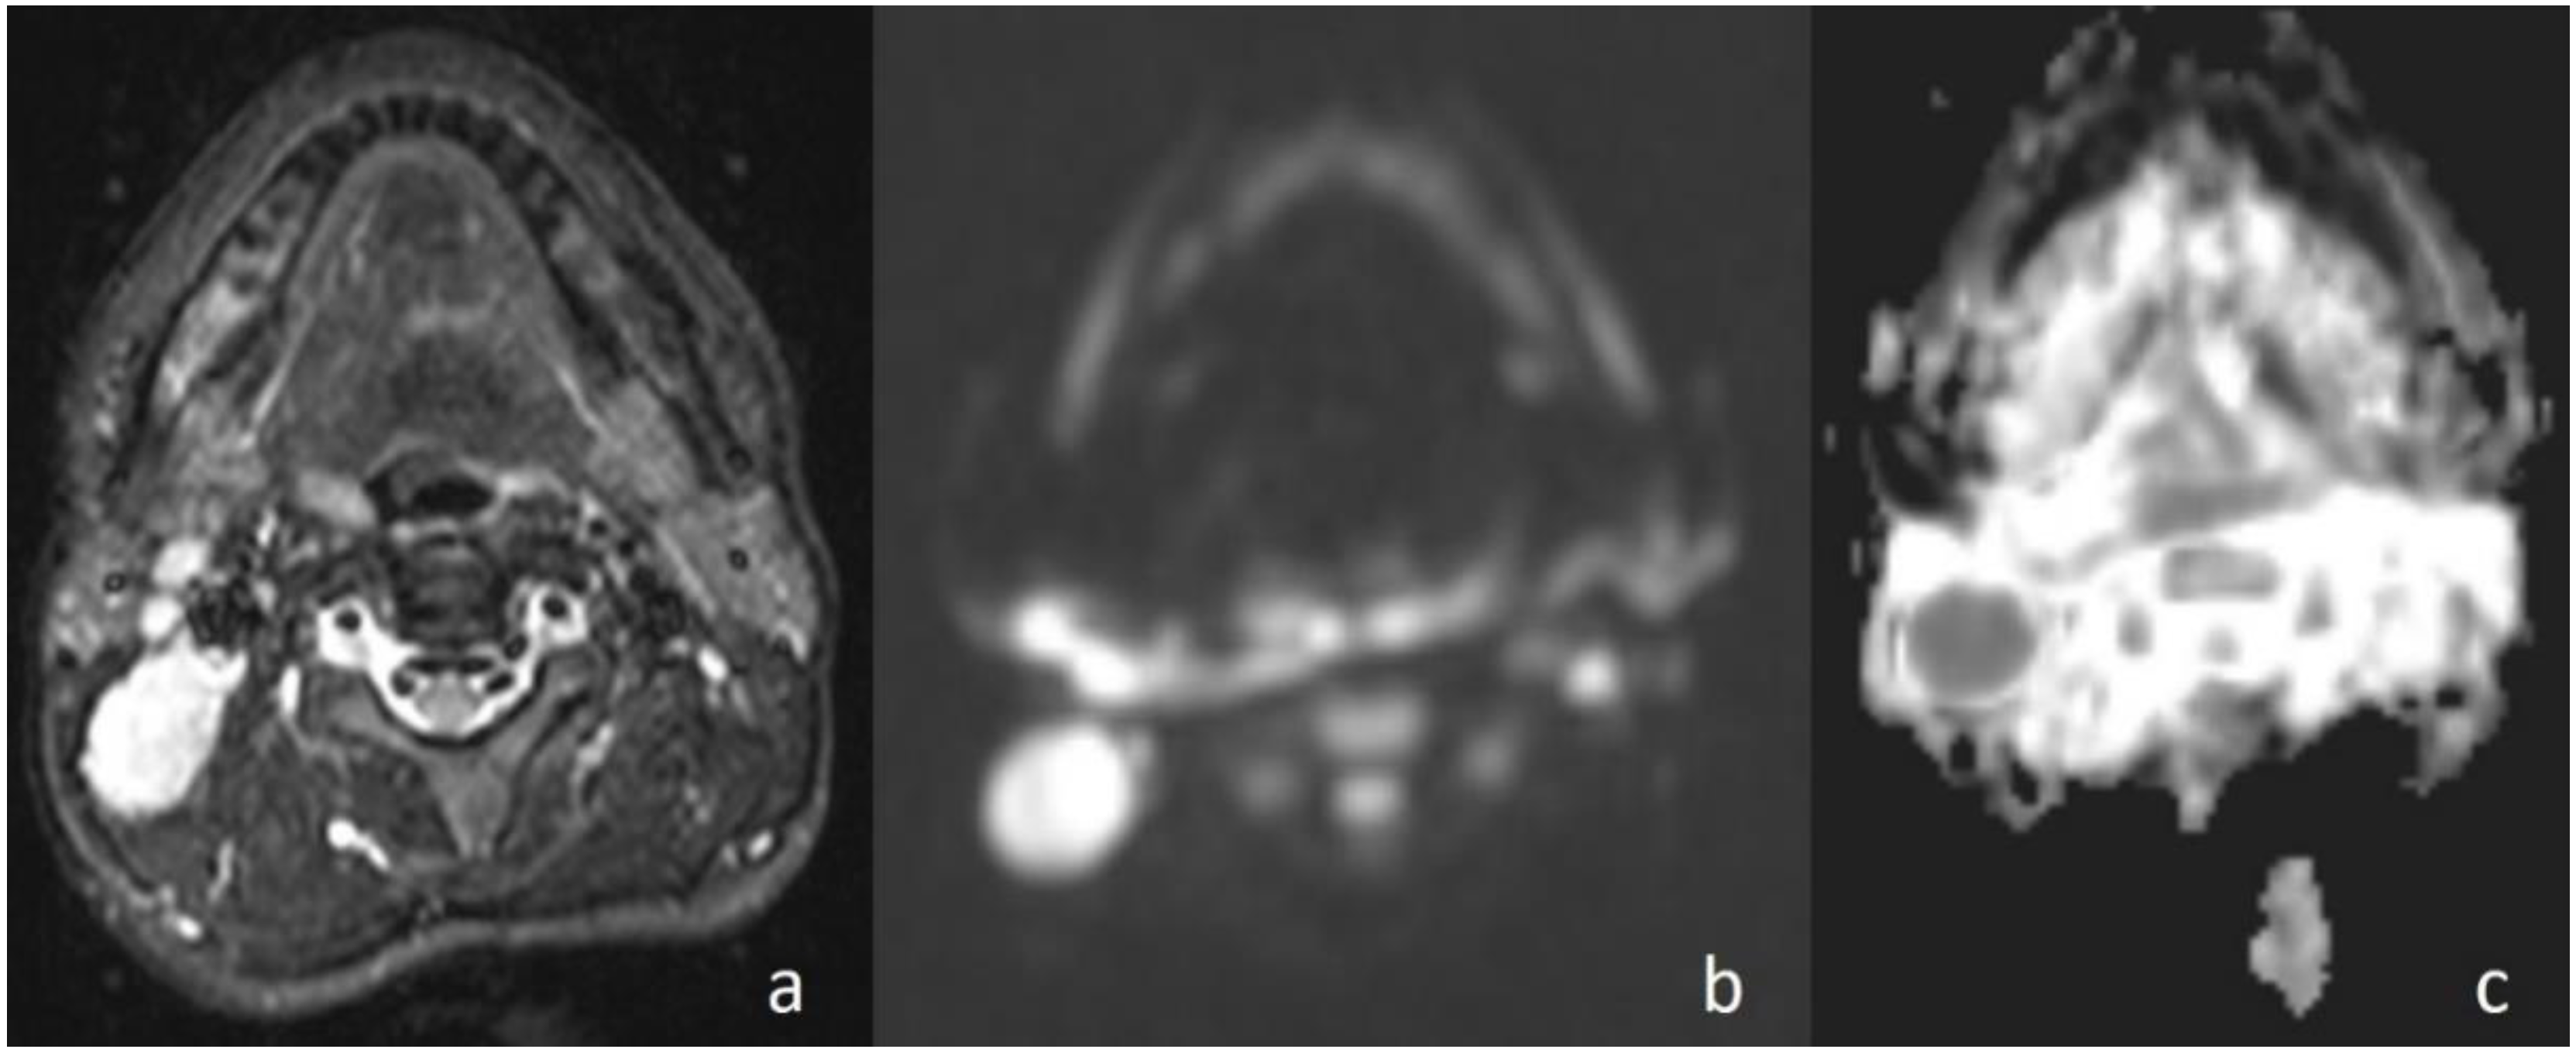

Figure 3. Undifferentiated nasopharyngeal carcinoma. (a) Axial T2WI shows bilateral metastatic cervical lymph nodes; (b) lymph node, on the left side of the neck, shows high signal intensity on DWI; and (c) the mass is hypointense on the ADC map (ADC value of 0.91 × 10−3 mm2/s).

In the current study, the mean ADC value of benign masses with high signal intensity was significantly (Figure 2) higher than that of malignant (Figure 3) masses with low signal intensity. These differences in ADC values may be explained by the differences in the histopathological characteristics of benign and malignant tumors. Generally, malignant tumors show hypercellularity and have enlarged nuclei, and hyperchromatism. These histopathological characteristics reduce the diffusion space of water protons in the extracellular and intracellular regions [13,14].